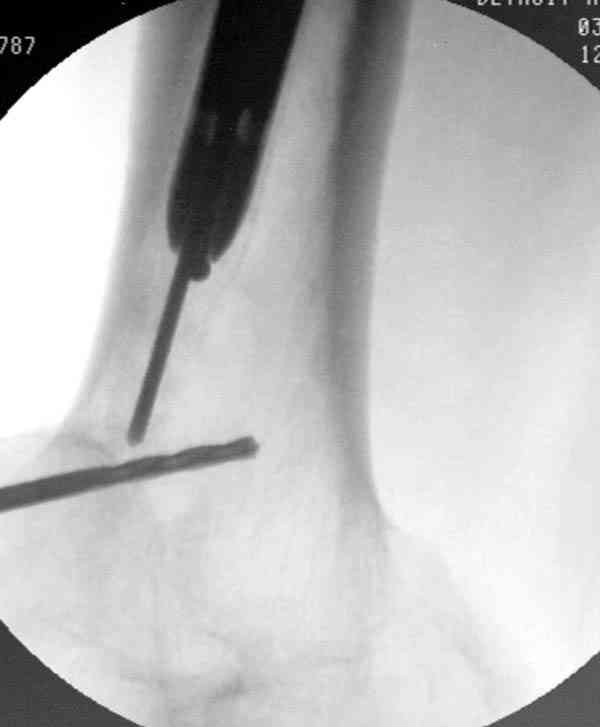

Периферический отломок стержня - наверно, надо воспользоваться отверстием, над ним сделать трепанацию и через него вверх провести длинную спицу, сделав на ее нижнем конце крючок. Лучше уже перед этим рассверлить центральный отломок.

Приспособление для удаления сломанных штифтов и наличие ЭОП облегчит задачу. При отсутствии крючка тогда можно применить обычный длинный ball pointed guide wire от интрамедулярного набора. Проволока, пропущенная за пределы гвоздя и зажатая другая вытащат сломанный конец штифта без проблем.